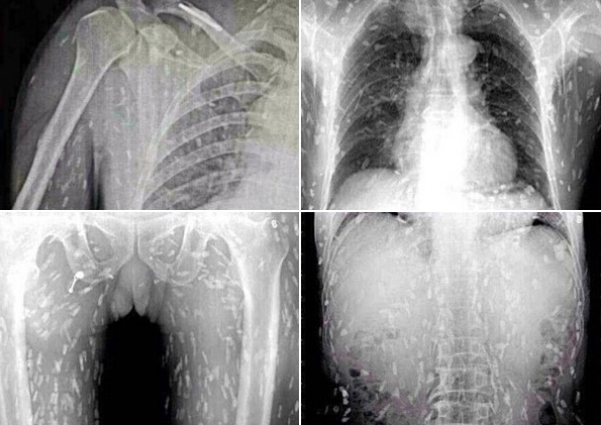

病院では頭部MRIと全身CTスキャンが行われたが、その検査結果は専門家さえも驚く衝撃的なものだった。それもそのはず、女性の全身はすでに無数の寄生虫に侵されており、大脳や顔面の筋肉にさえも感染が見られるひどい有様だったからだ。

医師の話では、女性の体内の寄生虫の一部はすでに死に、石灰化しており、全身の痛み以外に眼球突出や網膜出血といった症状も見られたとのこと。治療はすぐに行われたものの、一部の寄生虫は体外に排出されず、女性には後遺症が現れる可能性も否めないという。